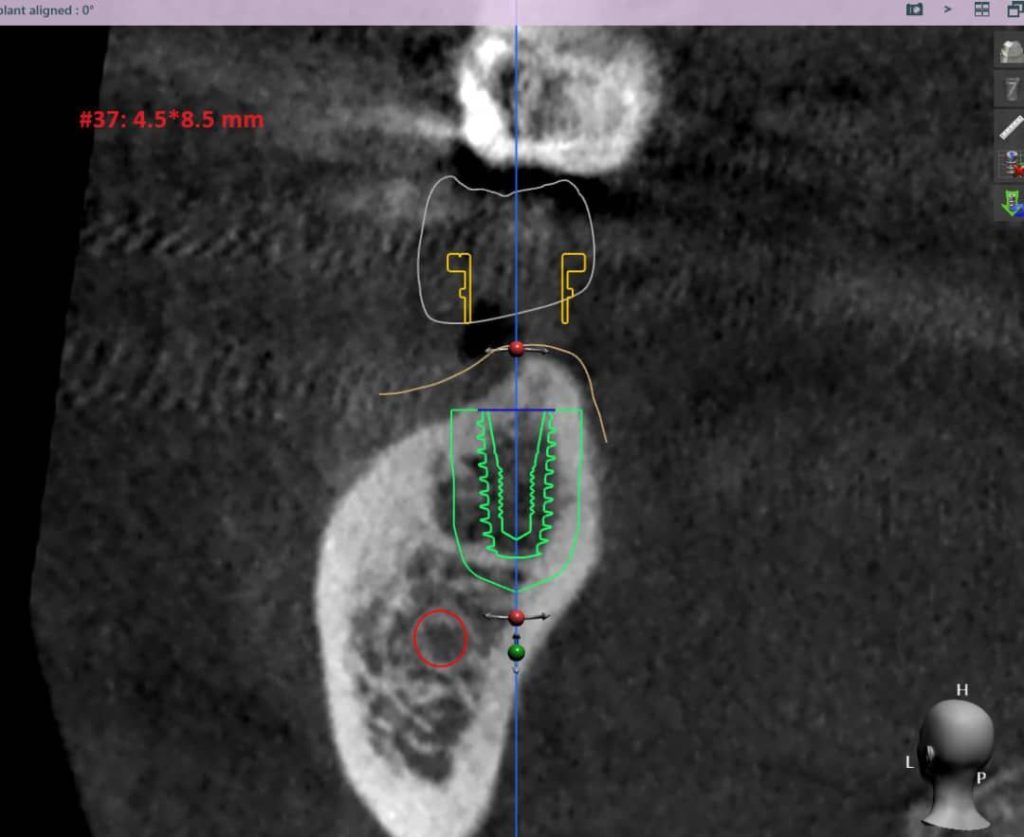

تصویربرداری سه بعدی( CBCT):

اسکن سه بعدی فک و دندان ها انجام میشود تا ساختارهای دقیق استخوان و موقعیت عصب ها مشخص شود

طراحی دیجیتال:

با استفاده از نرمافزارهای پیشرفته، محل قرارگیری دقیق ایمپلنت طراحی و شبیه سازی میشود

کاشت ایمپلنت:

عمل جراحی با استفاده از راهنمای جراحی و دستگاههای دیجیتال انجام میشود

طراحی پروتز دیجیتال:

تاج دندان نیز با دستگاههای CAD/CAMطراحی و ساخته میشود